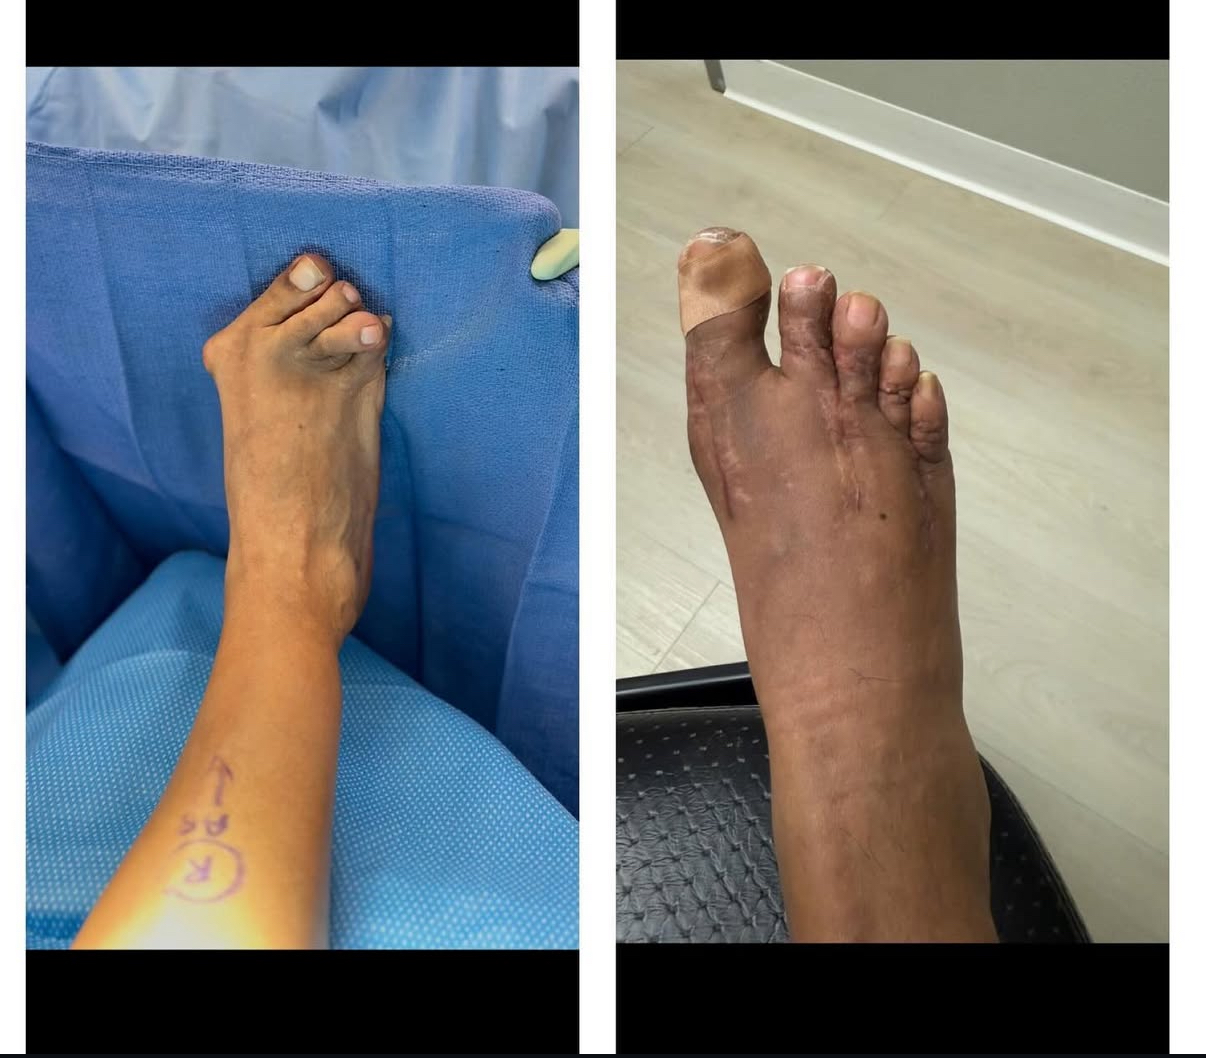

Ankle fracture repair

AF1

AF2